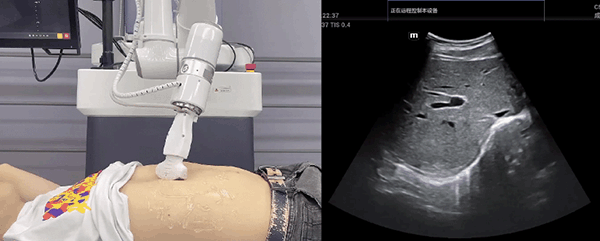

艾利特機(jī)器人末端搭載超聲探頭,可以對淺表小器官和外周血管、腹部(肝、膽、胰、腎等器官)進(jìn)行超聲檢查。

普羅超聲聚焦治療機(jī)器人

目前,艾利特機(jī)器人在生物醫(yī)藥、醫(yī)療健康領(lǐng)域的賦能已有顯著進(jìn)展,艾利特協(xié)作機(jī)器人應(yīng)用場景覆蓋了臨床試驗、試管檢測、拭子采集、試管搬運(yùn)、熒光檢測、康復(fù)治療、超聲掃查、導(dǎo)診、消毒、微創(chuàng)治療、針灸刮痧等。